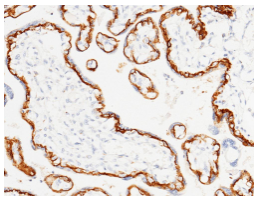

1【免疫组化】

检测TROP2在肿瘤和正常组织中的表达,信噪比高